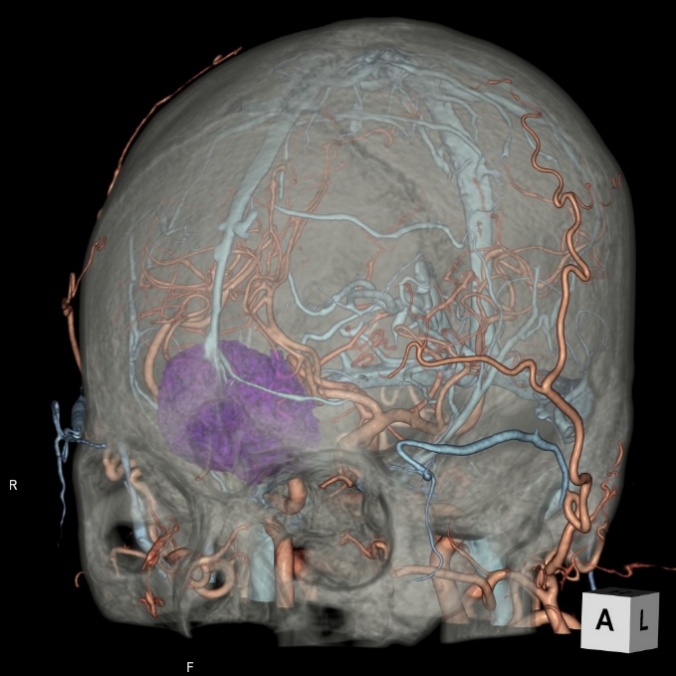

画像診断装置・放射線治療装置紹介

X線CT装置

64列 MDCT Aquilion CX (canon)

|

80列 MDCT Aquilion PRIME (canon)

80列 MDCT Aquilion PRIME SP(canon)

大きなトンネルの中に体を入れて、X線をあてて体の輪切りの写真を撮ります。CT検査には、単純CT検査と、造影剤を注射して撮影する造影CT検査があります。